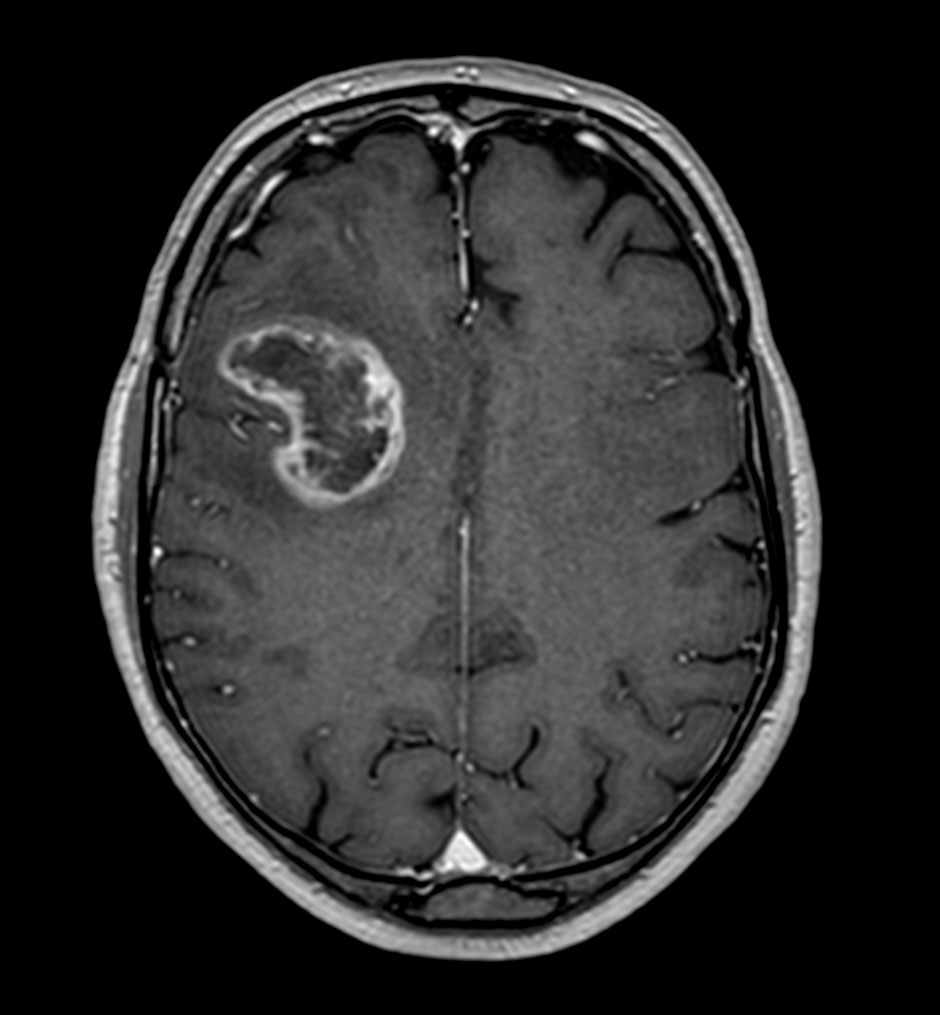

Axial 3D T1w TFE

Axial 3D T1w TFE with gado